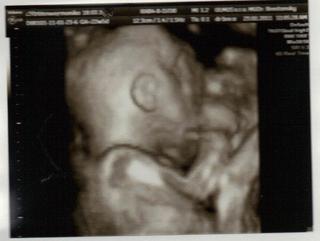

dnes sme boli na tom 4D... no naša malá potvora sa nám ukázala iba na malinkú chvíľočku a potom ani za nič 😀

tak o 2 týždne ideme zasa ale už ju nebude merať už iba kvôli videu aby sme mali peknučké lebo teraz nie je skoro nič v 4 D , lebo to nebolo riadne vidieť.. Keď to mmm donahráva na youtube hodím vám sem link.. malo by to ešte takých 20 minút trvať.

Malinká je krásna a váži cca 572 g 😀 Zodpovedáme 23 tt a 2 d.. sme 22 tt a 5 d... takže je to ok 🙂

STále mala ručičku pred tváričkou 😀

@alena24 - vidím, že váš je ako naša .-D tiež tie ruky pred tvárou. ale aspoň zo začiatku na chvíľu ukázala.. 😀

o 2 týždne si to zopakujeme. som zvedavá či to aj ona zopakuje 😀

@monika0001 ako je dobre vidiet, ze je to dievcatko...som si nemyslela, ze sa to da az tak dobre... ked clovek cita ako sa lekari uz viackrat pomylili a povedali, ze dievcatko a zrazu to bol chalan....

my sme pri prvom sice nemali pochybnosti, ale to preto, ze predsa len pipik trcal dost vela... 😀 Ale teraz vidim, ze aj dievcatko sa da urcit velmi presne.... tak sa tesim...na 3D/4D idem 1.2.